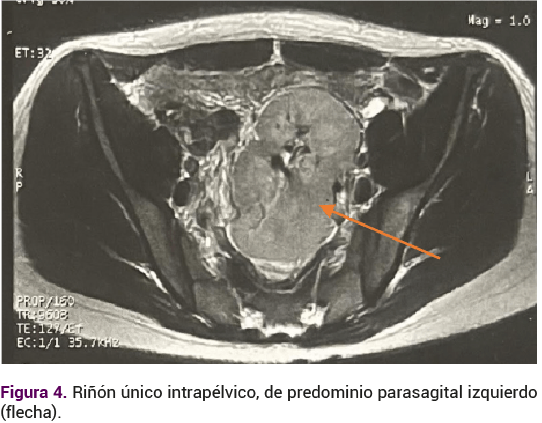

El ultrasonido renal reportó ectopia renal cruzada, de apariencia fusionada con el uréter distal único. El ultrasonido pélvico reportó la ausencia del útero y de los ovarios. El perfil hormonal se informó con: FSH 4.39 mUI/mL, LH 2.89 mUI/mL, estradiol 80.5 pg/mL, androstenediona 1.27 ng/mL, testosterona total 0.2 pg/mL, prolactina 14.2 ng/mL, TSH 1.1 mUI/mL. La resonancia magnética reportó: ausencia de útero, ambos ovarios con desplazamiento cefálico, sin evidencia de imagen que sugiriera el canal vaginal (Figura 3). Riñón único intrapélvico parasagital izquierdo (Figura 4) con diagnóstico por imagen tomográfica de ectopia renal cruzada y agenesia úterovaginal.

Alteraciones renales: agenesia unilateral, ectopia o riñón en herradura. El riñón ectópico es la alteración más frecuente 40-50% (con riñón contralateral normal 30%, ausente 12%). Agenesia renal 43%. Anomalías de la pelvis renal o uréteres 12%. Atrofia renal 5%.4,21,22